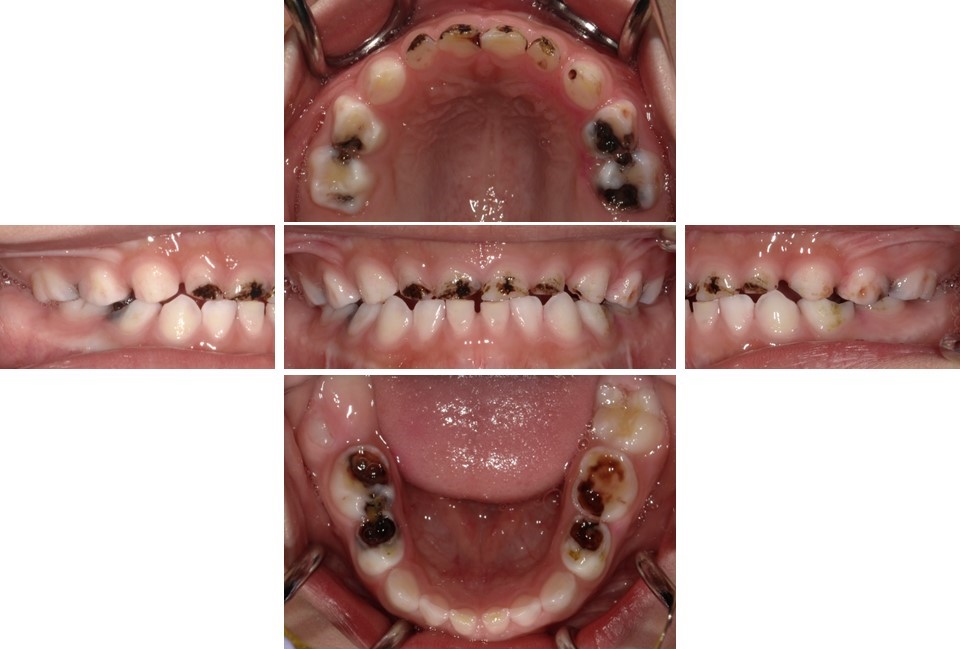

子どものう蝕の数は年々減少しており、う蝕の全くない子どもが多くいますが(図2)、重度のう蝕を有する子どもが一定程度存在し続けています(図3)。3歳まではう蝕がないことが一般的であり、この頃までに既にう蝕がある子どもに対しては、将来的にう蝕リスクが高い対象として、特に配慮していく必要があります。子どものう蝕の発生に影響する要因として口腔清掃不良が挙げられますが、砂糖の摂取に関連した不適切な生活習慣にも注目する必要があります。う蝕になりやすいのは、ほとんど唾液が分泌されず自浄作用が低下する「就寝時」です。そこで、就寝前に適切な口腔清掃を行うことが重要であり、砂糖を含む食品の摂取を控えるように指導してください。

(図3)重度のう蝕を有する小児(5歳9か月男児)